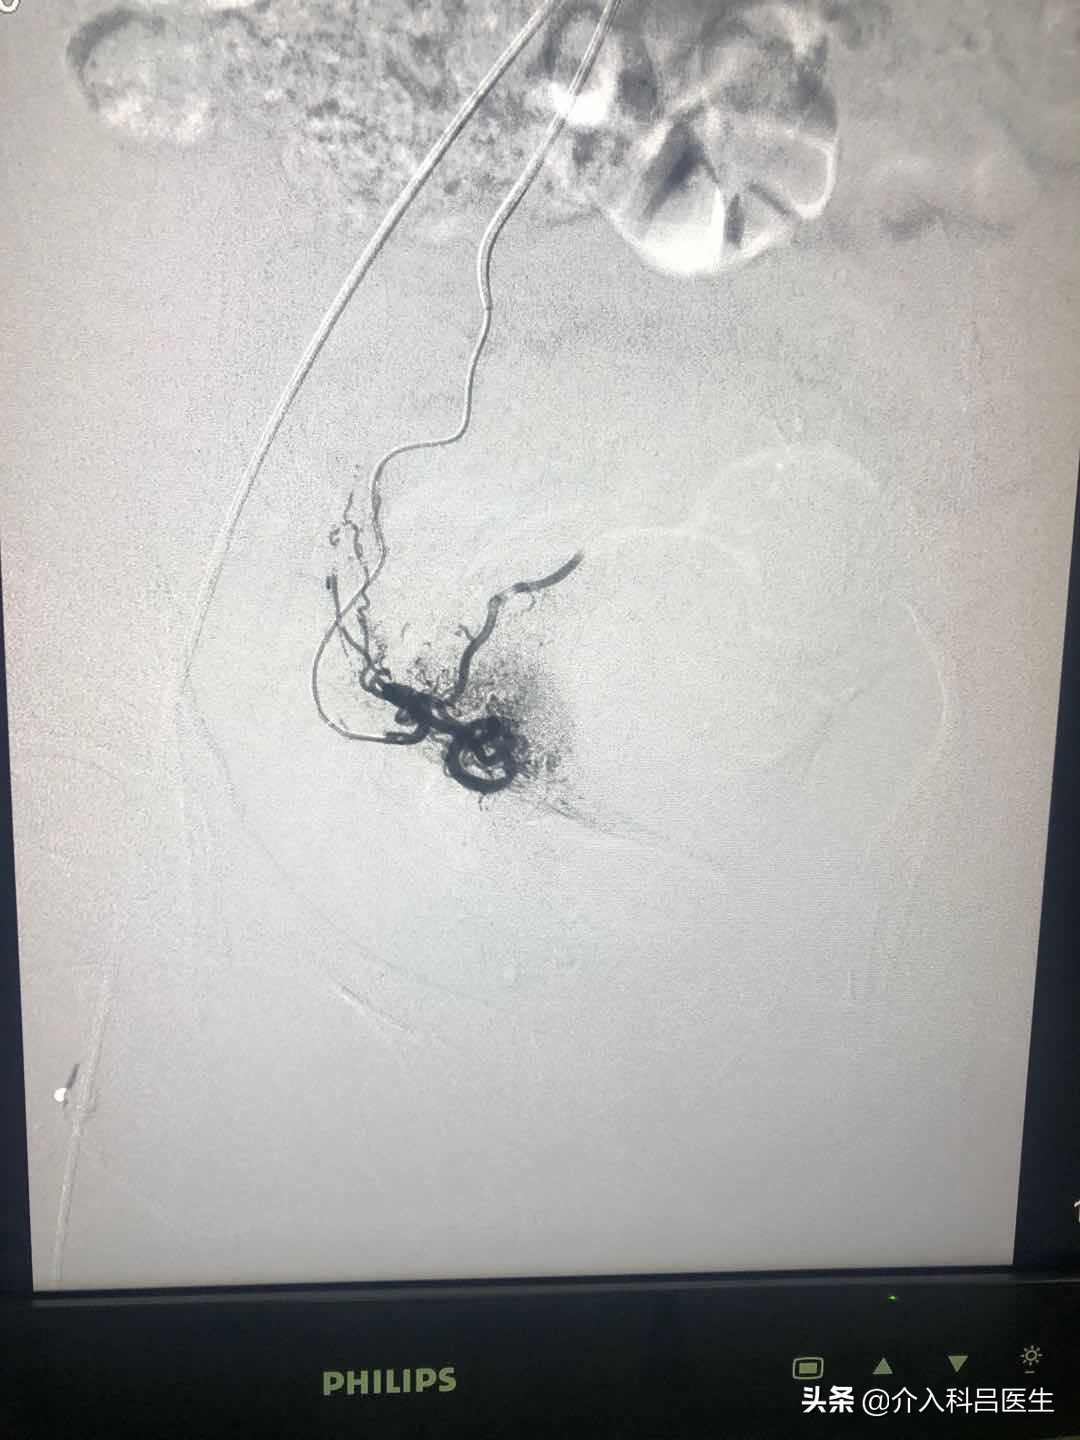

囊肿术后,再用针穿刺到子宫动脉,栓塞腺肌症病灶的供血血管,病灶因为缺血萎缩,大概三四个月后,子宫体积慢慢恢复,子宫内的环境也慢慢改变。然后再养一段时间,患者说不定就能“圆梦怀孕”。